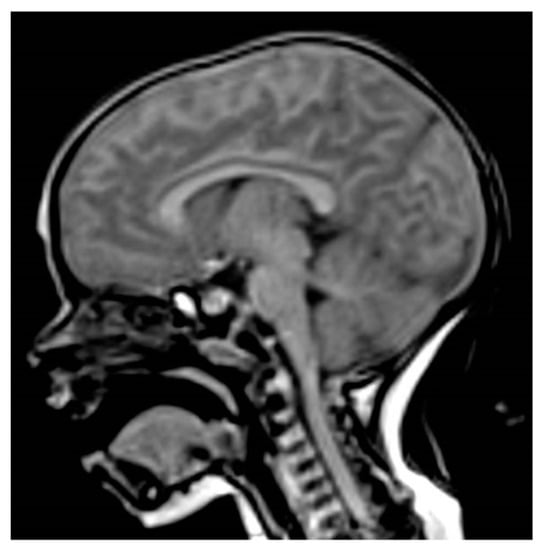

Pituitary magnetic resonance imaging (MRI) showed a T1 hyper-intense enlarged anterior pituitary (height 9 mm), symmetrical region with a patchy signal and low enhancement after contrast agent (gadolinium) injection, with no abnormalities in the pituitary stalk or the optic chiasm, and a normal posterior pituitary bright spot (Figure 1). Brain MRI was performed using a 3 Tesla magnet (Samsung, Seregno [MB], Italy). Sequences were acquired according to multiple planes and a thin layer on the diencephalon-pituitary region. The sequences were obtained before and after the intravenous administration of paramagnetic contrast medium (Dotarem 0.5 mmol/mL, tot 2.6 mL) with suppression of the adipose tissue signal.

Figure 1. Sagittal pituitary MRI image showing hyper-intense enlarged anterior pituitary (T1-weighted sequence).

All patients with PIT1 mutations and most patients with PROP1 mutations have either small or normal-sized anterior pituitary glands, but some patients carrying PROP1 mutations can present normal-sized or hypoplastic or even enlarged pituitary glands. Several patients with PROP1 mutations and pituitary enlargement are usually observed in early childhood, which is followed by pituitary hypoplasia [14]. The 301,302delAG mutation is the most frequent mutation and most patients with pituitary enlargement have been shown to harbor the 301–302delAG mutation. However, 150delA, Q83X, and R73C mutations have also been described as associated with pituitary enlargement. Usually, pituitary enlargement is followed by a waxing and waning size of the pituitary mass with hypoplastic pituitary at the end. In addition, the same mutation in siblings can occur with different pituitary morphologies [14]. Our case underlines the importance of MRI imaging in the diagnosis of children with hypopituitarism [6]. Differences in MRI pituitary gland morphology can suggest different GHD etiologies and prognoses. In our patient, the finding of an enlarged pituitary in a non-syndromic infant with two pituitary hormone deficiencies suggested a PROP 1 defect. Pituitary enlargement is sometimes dramatic but has a benign course and is followed by degeneration and regression [12]. Under such conditions, genetic testing offers an important tool for making therapeutic decisions in patients with pituitary mass and is indispensable in avoiding unnecessary neurosurgery [13].